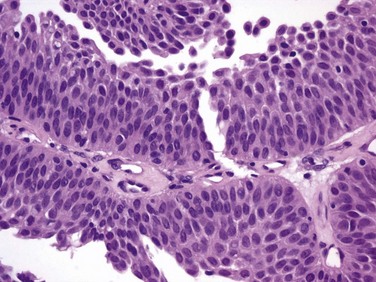

In contrast, essentially benign papillary tumors with orderly cellular arrangement, minimal architectural abnormalities, and minimal nuclear atypia are distinct from those two grades and are designated Papillary Urothelial Neoplasm of Low Malignant Potential (PUNLMP). Such tumors would have been labeled either papillomas or grade 1 TCC in older systems but are now regarded as so unlikely to progress that they are considered benign. However, on the basis of this low risk, the WHO recommends that such pathology reports contain the note, “Patients with these tumors are at risk of developing new bladder tumors (“recurrence”), usually of similar histology. However, occasionally these subsequent lesions manifest as UC, such that follow-up of the patient is warranted” (Epstein et al, 1998). Papillomas are truly benign and not associated with risk of progression (Figs. 81-1 through 81-5).

Figure 81–2 The urothelium is thickened, but cells and nuclei are normal in papillary urothelial neoplasm of low malignant potential (×40).

Figure 81–3 Ta low-grade tumor (×40). Cells are relatively normal but exhibit irregularity and some nuclear differentiation.